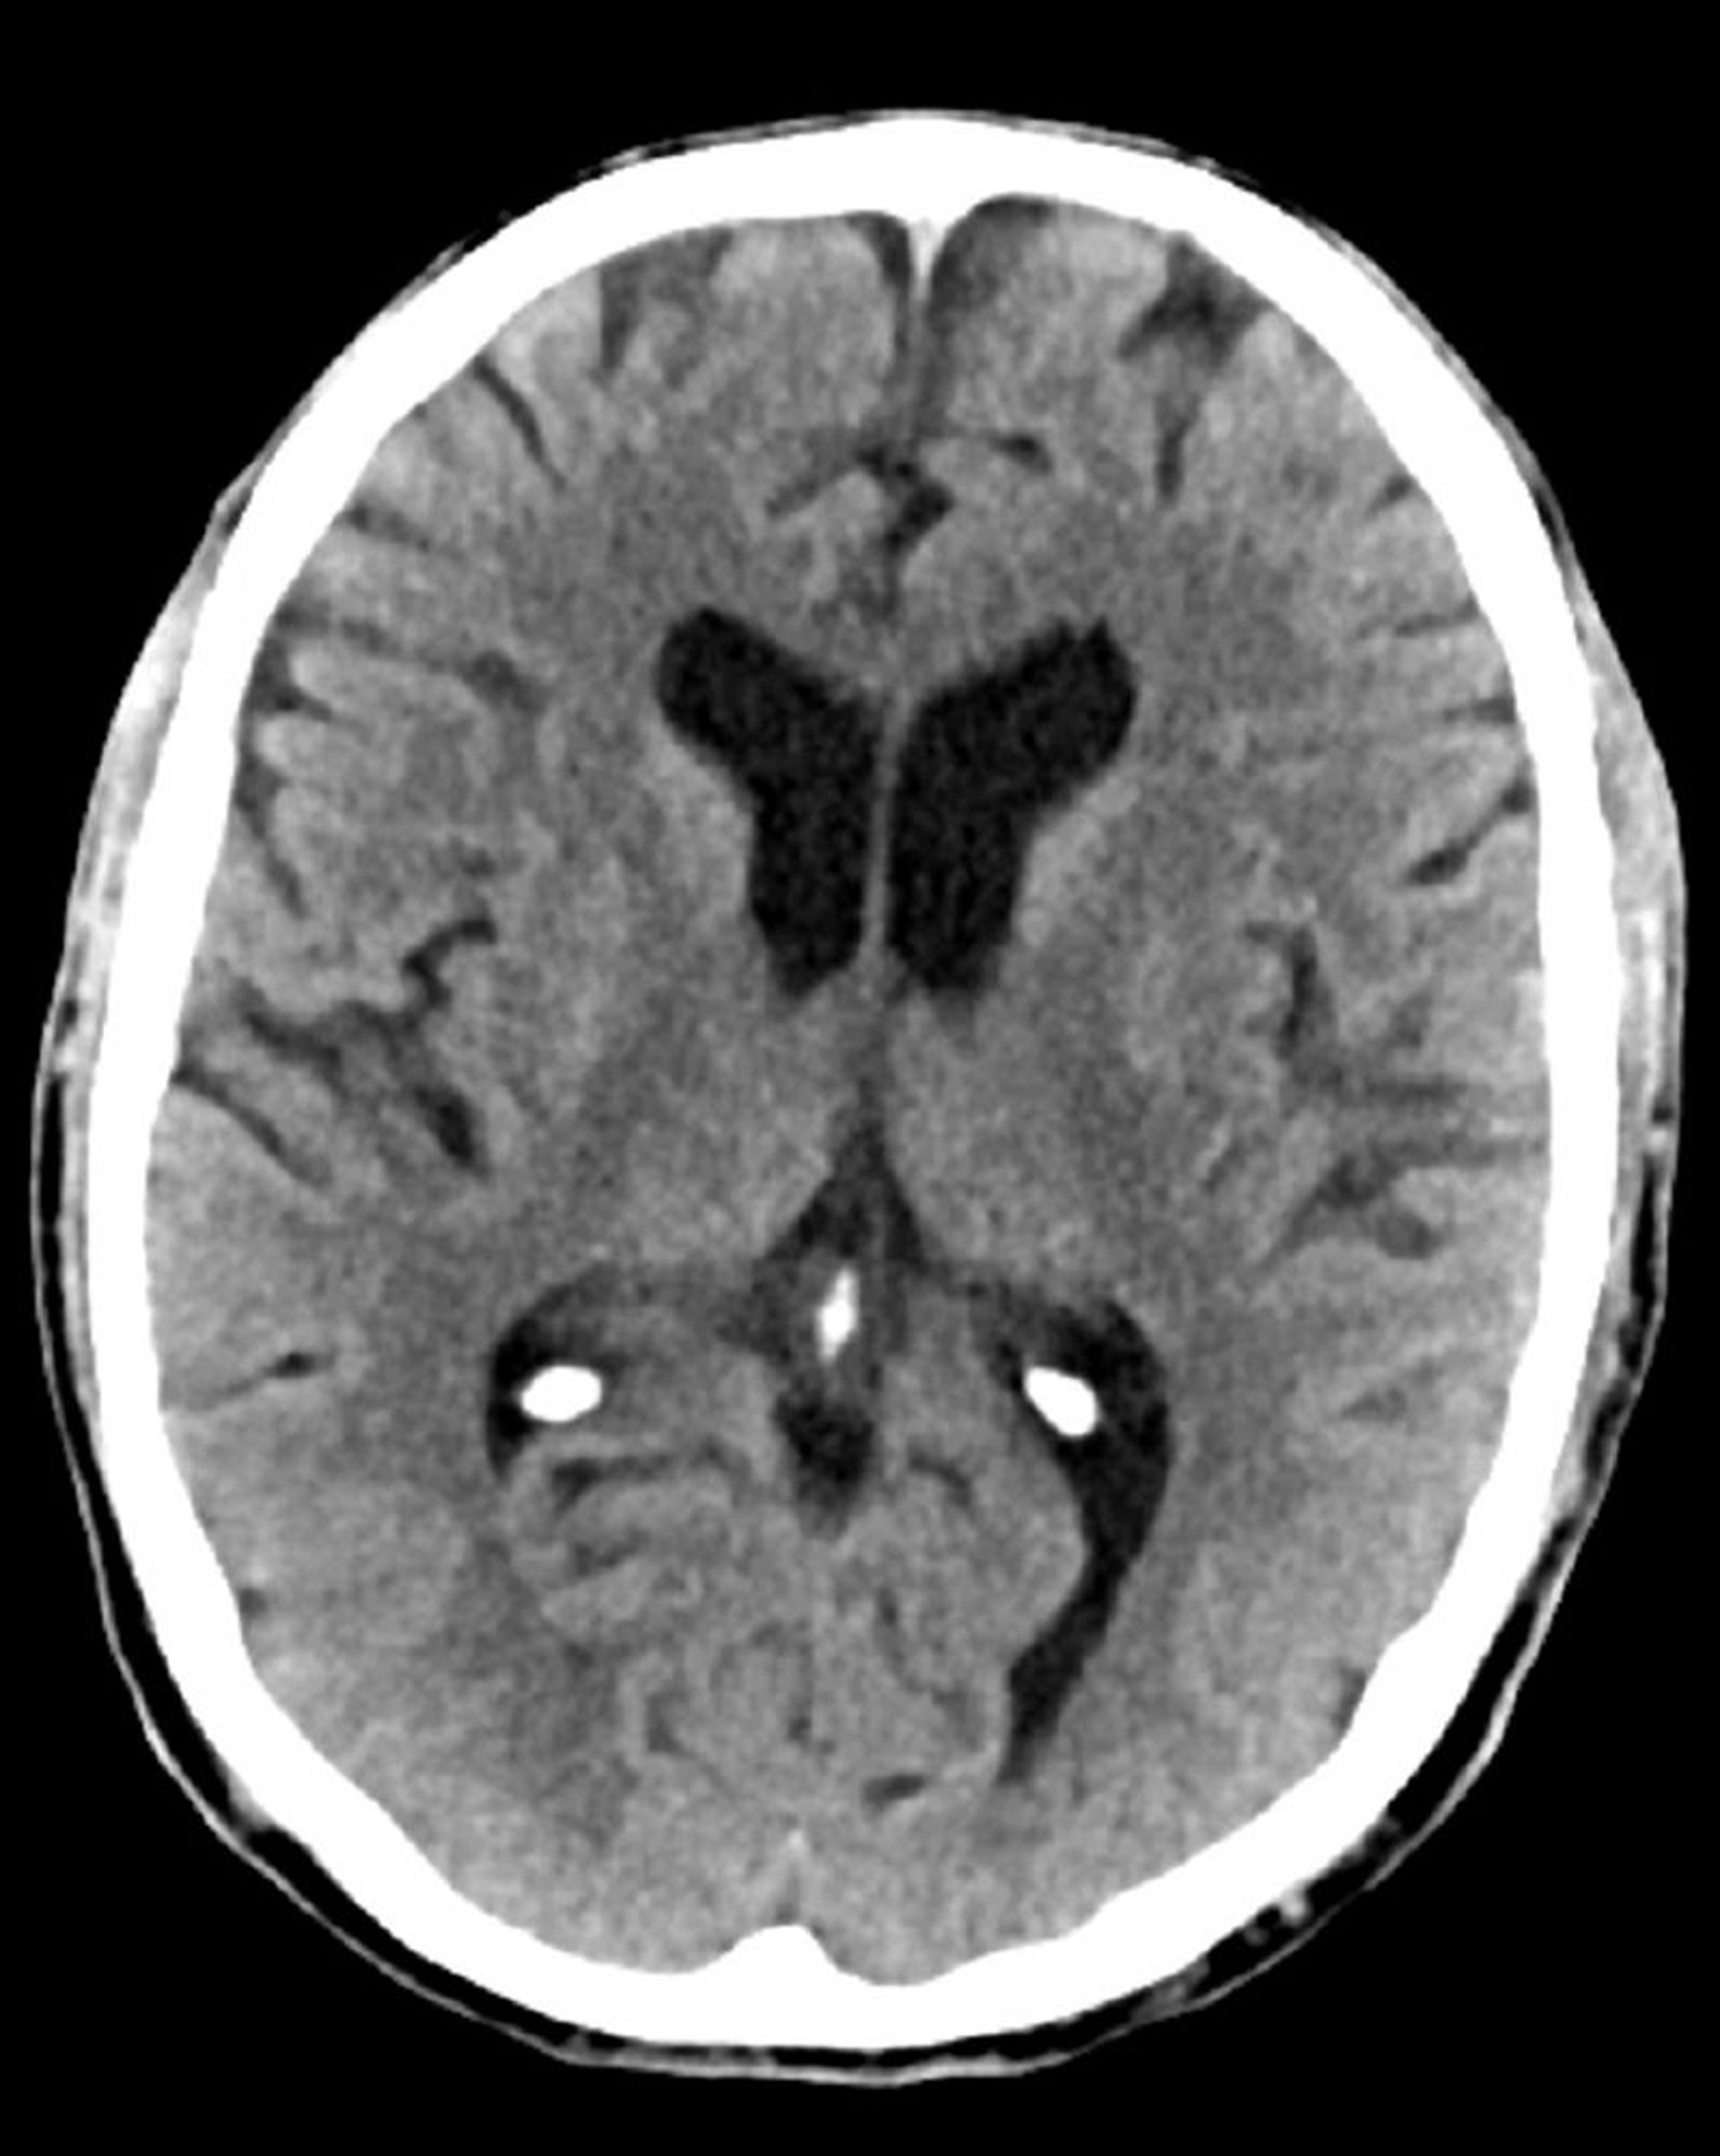

正常な頭部CT(成人,74歳)―スライド5

これは74歳成人の正常な頭部CT画像である。30歳の正常な頭部CT画像と比較すると,脳室および脳溝がより大きくなっている。これらの所見はこの年齢層では正常である。